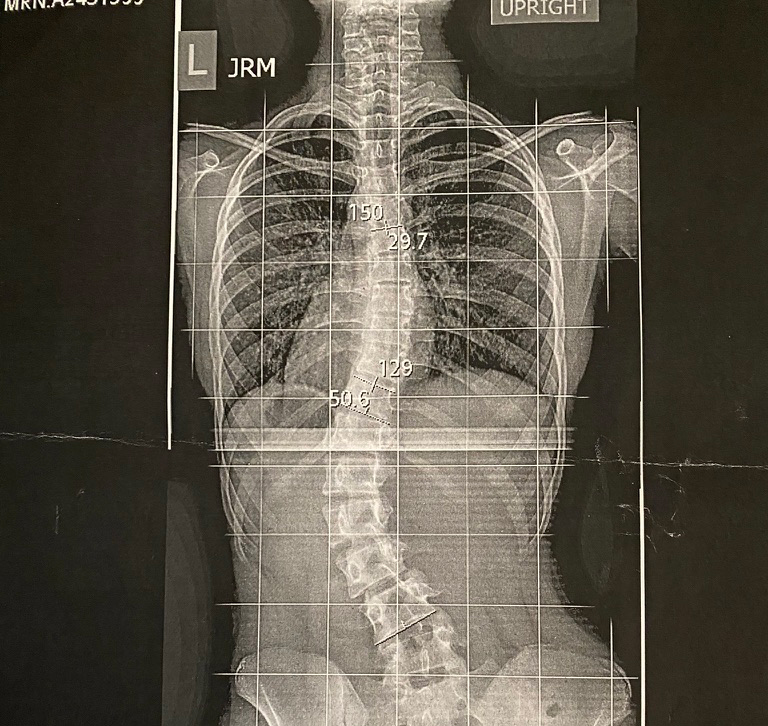

Everything took a turn for the worse when in 8th grade I went for my routine checkup and found out the brace hadn’t worked. My spine had a 50 degree curve in the lumbar region and a 30 degree curve at the top. Surgery was inevitable. My head started to spin and my hands started to tremble as I felt the anxiety start to arise. Surgery was scheduled the summer before my freshman year to ensure I had enough time to recover before the school year because of the 6 month recovery time.

Ultimately, the surgery was unavoidable and on July 23, 2022 I underwent the spinal fusion procedure. I had two titanium rods inserted in my back fusing seven vertebrate in my spine. The surgery included 5 grueling days in the ICU and months of recovery. I was unable to do anything on my own for weeks. I could not walk on my own, bathe or even use the rest room without assistance. Everything was a struggle.